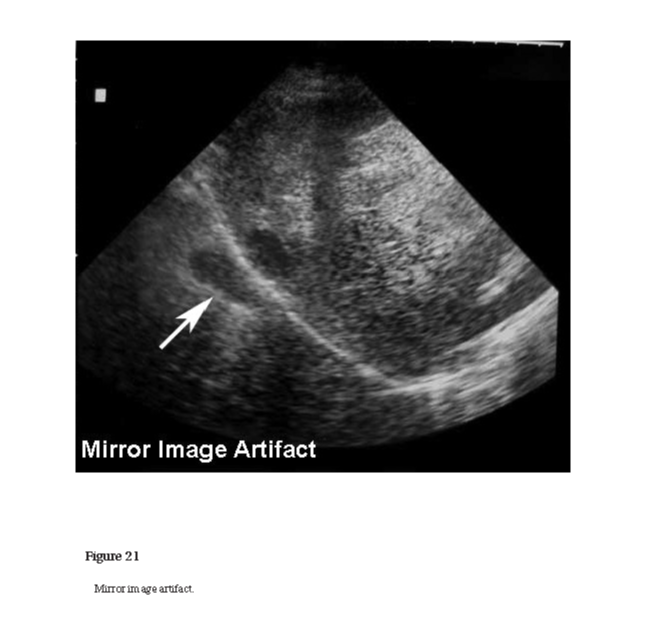

artifact

An anomaly in an ultrasound image that does not correspond to an actual anatomical structure or target. Artifacts can manifest as additional echoes, distortions, or missing information due to the interaction of ultrasound waves with tissues or structures. Reverberations and shadowing are examples of such artifacts (see Figures 15, 16, 21, 22, 23, and 24).

Figure 15 Figure 16 Figure 21 Figure 22 Figure 23 Figure 24